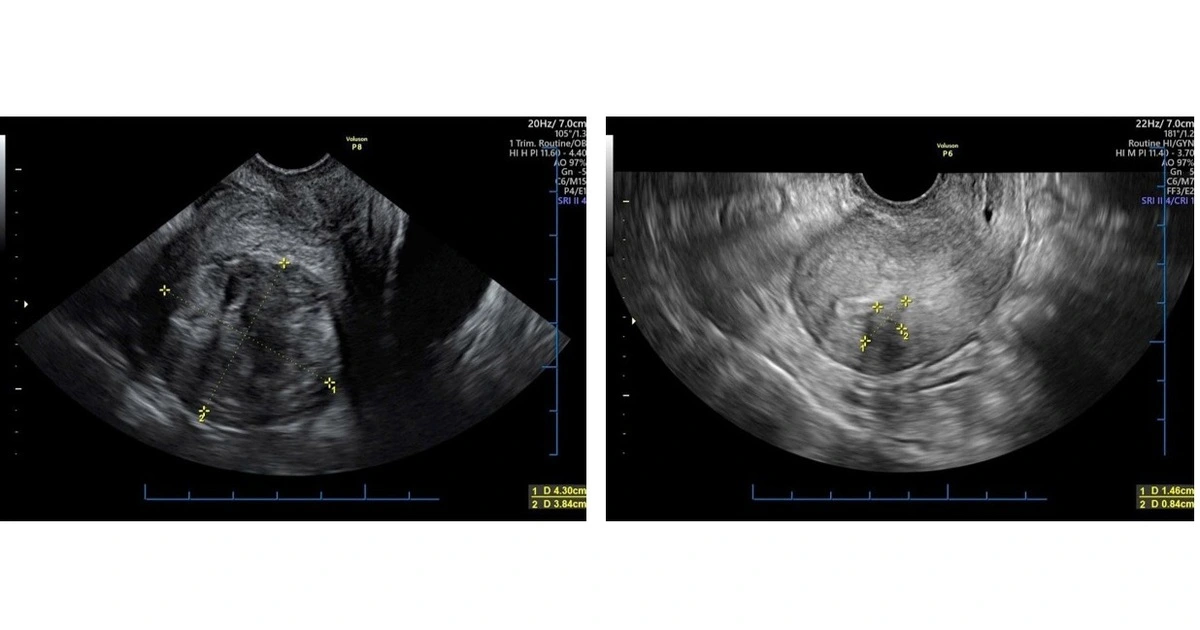

Điều trị u tử cung không xâm lấn, bảo tồn chức năng sinh sản

Theo GS-TS Nguyễn Viết Tiến, nguyên Giám đốc Bệnh viện Phụ sản T.Ư, Phó chủ tịch Tổng hội Y học VN, các khối u phụ khoa gây ảnh hưởng lớn đến sức khỏe và chất lượng sống của phụ nữ.